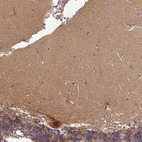

Immunohistochemical staining of human cerebellum shows strong cytoplasmic and nuclear positivity in Purkinje cells.